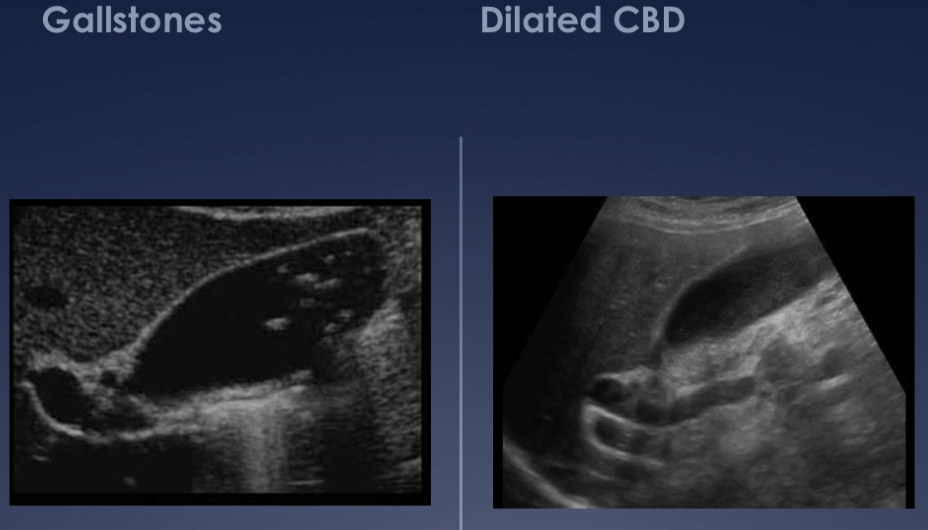

Why is an ultrasound used for abdominal imaging, and what is it most commonly used to image?